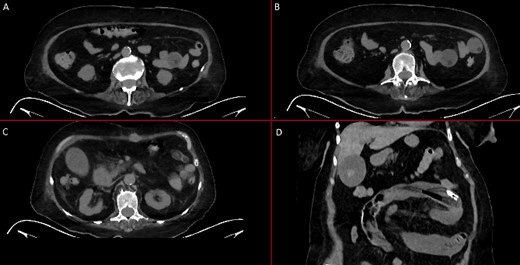

With these findings, an upper endoscopy revealed two gauzes in the antrum; however, the gastrostomy tube was nowhere to be found (Fig. 1). Due to this, an abdominal computed tomography was needed, revealing that within the small bowel, the 24-fr Foley catheter with the inflated balloon was found near the ileocecal valve (Fig. 2).

Abdominal CT. (A) An inflated balloon of the Foley catheter is seen in the bowel. (B) An inflated balloon of the Foley catheter is seen in the bowel causing obstruction. (C) The Foley catheter is seen inside bowel loops. (D) Foley catheter inside the bowel.